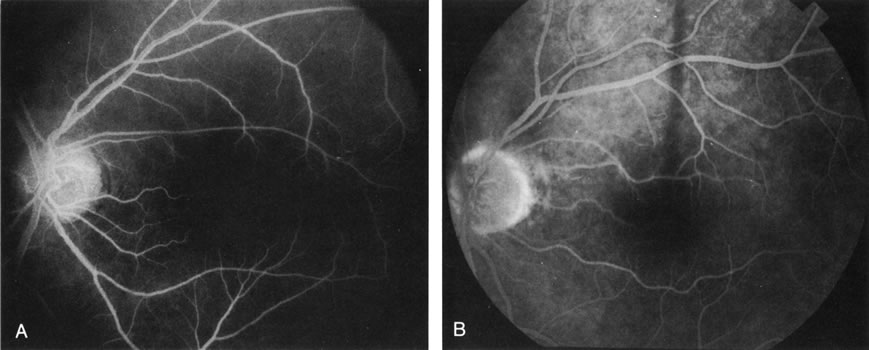

Furthermore, FA helps in recognizing two types of CNV: classic and occult. Classic CNV consists of a well-defined neovascular membrane, which is apparent in the early phase of the angiogram and shows late leakage of dye beyond its boundaries (Fig. 7 and 8). Occult CNV is seen on by FA as an area of late hyperfluorescence of undefined origin or as a neovascularized PED (Fig. 9 and 10 ). Mixed-type CNV is predominately classic or minimally classic depending on whether the classic component is more or less than 50% of the entire lesion (Fig. 11).

Fig. 7. Composite photograph of fluorescein angiography study in a patient with classic, subfoveal choroidal neovascularization (CNV) in the right eye. A The classic neovascular membrane appears as a well-defined area of hyperfluorescence in the early phases of the angiogram. There is leakage of dye from the classic net in the subretinal space throughout the study. B. In the late phase of the study, the edges of the CNV are fuzzy and indistinguishable.

Fig. 8. A. Color photograph of subfoveal classic choroidal neovascularization (CNV). The neovascular membrane appears as a dirty gray, subfoveal lesion surrounded by exudative neurosensory detachment. B–D. Fluorescein angiography demonstrates early hyperfluorescence and late leakage of the CNV.